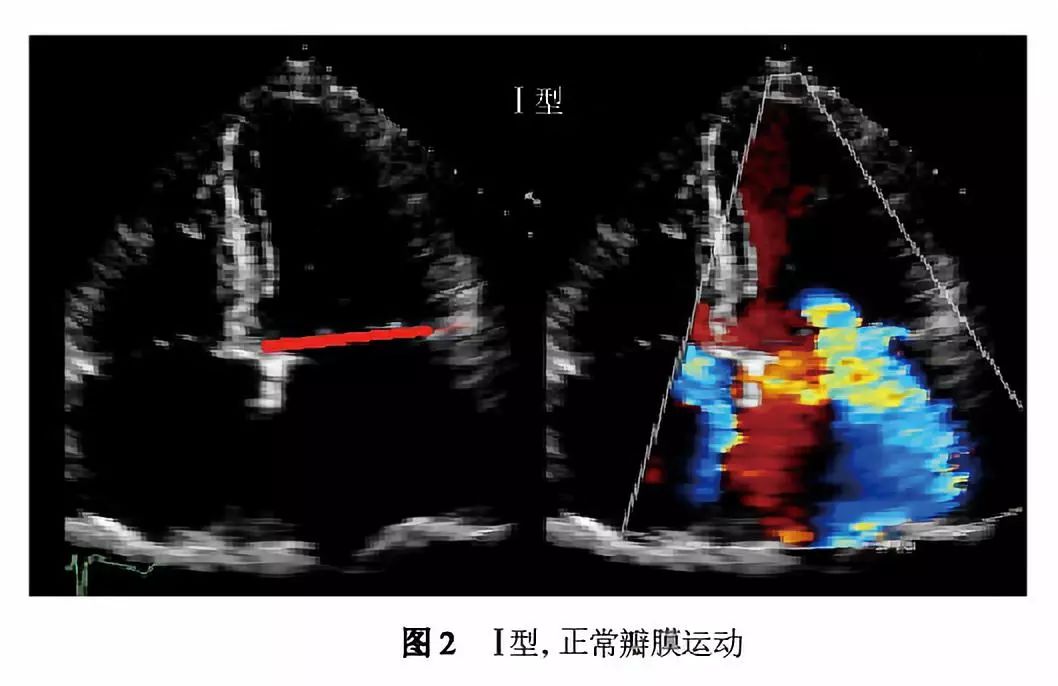

Ⅰ型:瓣叶活动正常而瓣膜功能失调(图2)。在Ⅰ型功能失调中,收缩期和舒张期瓣叶活动幅度正常,反流的原因为瓣叶穿孔或瓣叶对合不良导致(瓣环扩张)。